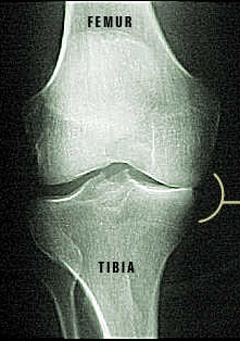

X-ray of Damaged Knee Joint

Notice how the femur is rubbing against the tibia. That is because the cartilage on top of the tibia has been damaged. Since only one side is affected, a partial knee surgery is possible.